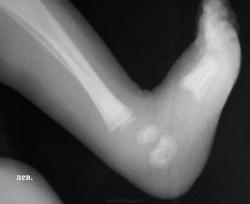

В проксимальных метафизах большеберцовых - такие же полоски.

Давно не встречалась с врожденным костным сифилисом, лет 10, позабылось все (раньше, в другой больнице, видела его достаточно часто), но что могу сказать - полосы просветления в метафизах (а также полосатость ядер окостенения пяточной и таранной костей) встречаются не только при сифилисе, часто видела их у здоровых недоношенных;  при сифилисе, кроме этих полос, должно быть расширение и зазубренность зон предварительного обызвествления, симметрично в костях голеней и предплечий, клинически, обычно, не проявляется, только при третьей стадии остеохондрита, когда появляются псевдопараличи Парро - появляется припухлость, отек, ограничение движений, и это также с обеих сторон. Здесь мне видится нечеткость метафиза малоберцовой кости слева, скорее всего, обычный остеомиелит. Конечно, анализ на сифилис, все-равно, заказать надо.

Сильно смущают пяточные и таранные кости - нигде не нашел, чтоб в них остеохондрит встречался...